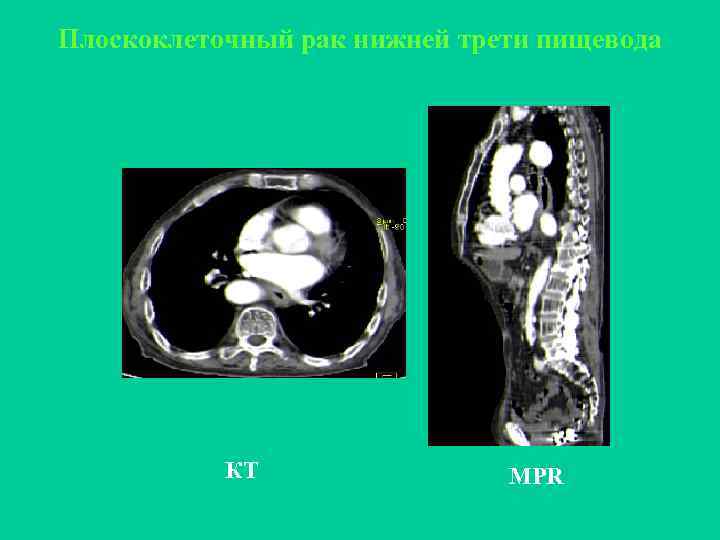

Плоскоклеточный рак средней трети пищевода

Плоскоклеточный рак нижней трети пищевода КТ MPR